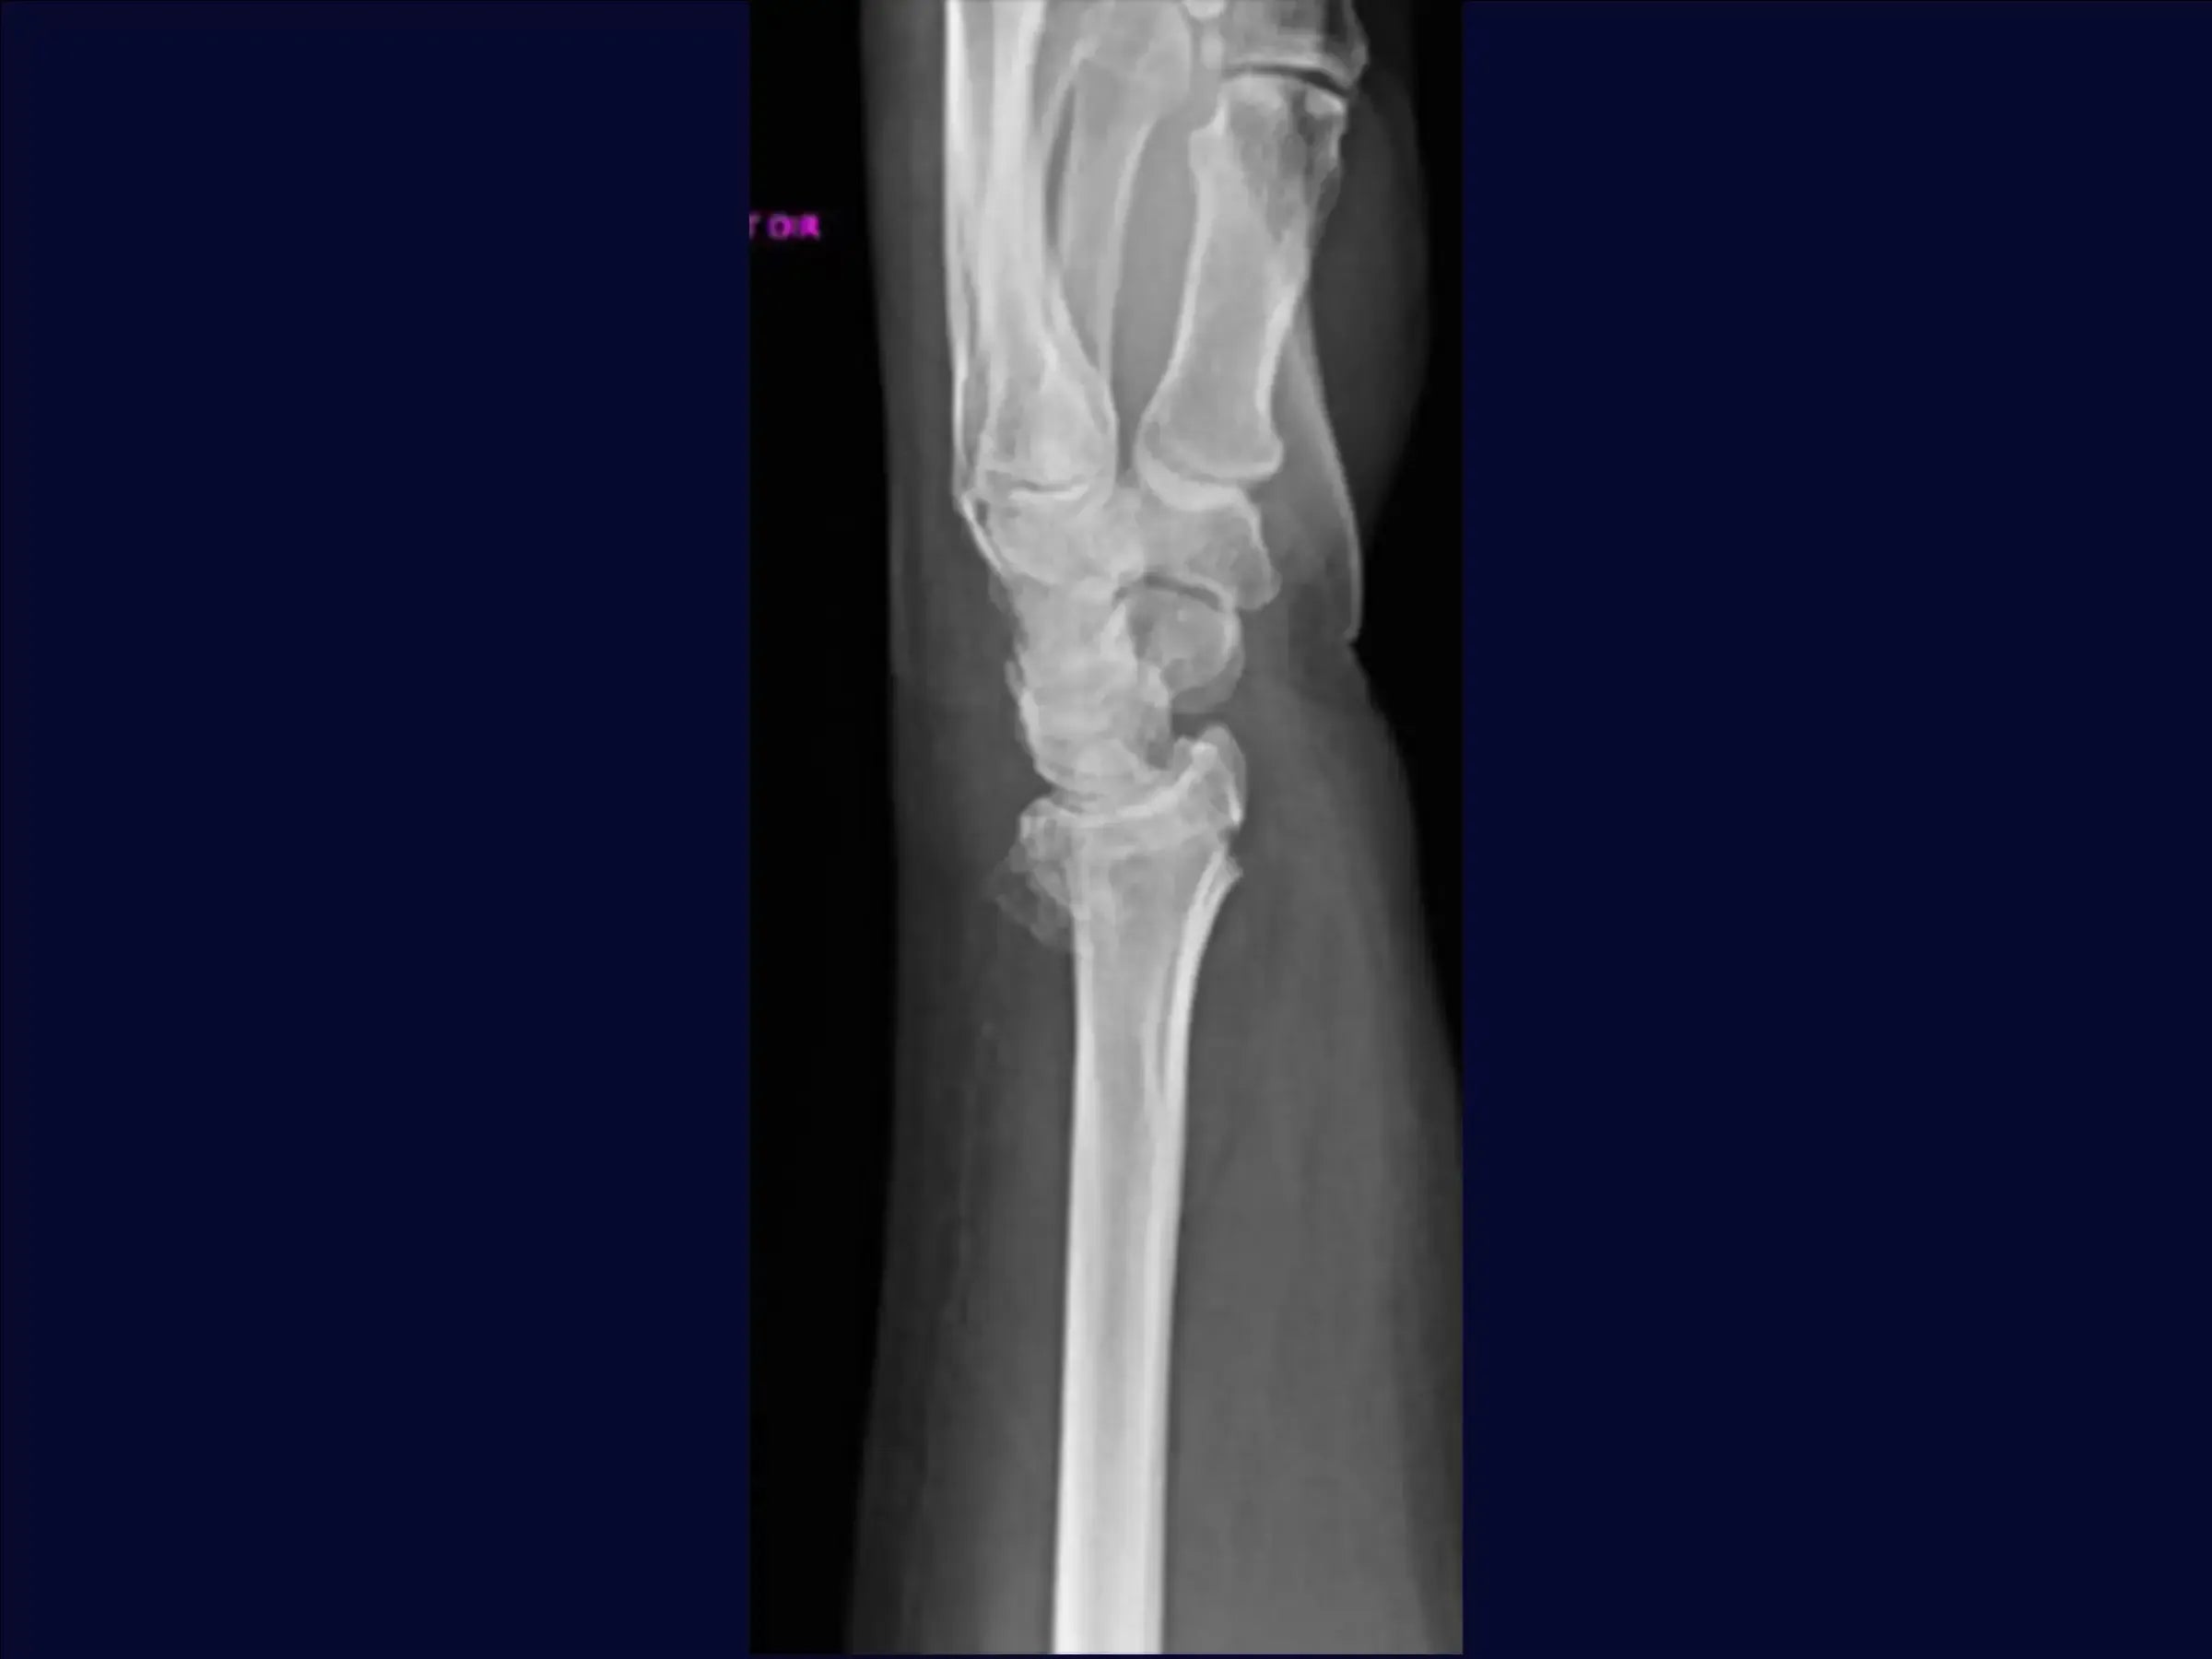

Domine o tratamento cirúrgico de fraturas do terço distal do rádio com cominuição dorsal e volar, e desvio dorsal. Este treinamento oferece uma imersão prática em uma abordagem volar, iniciando com fixação provisória da fratura, seguida pela dissecção cuidadosa dos planos e tendões, até a osteossíntese com placa, visando a redução anatômica e a estabilidade para a recuperação funcional do paciente.

- Tratamento cirúrgico de fraturas do terço distal do rádio com cominuição e desvio dorsal.

- Abordagem volar para redução e fixação.

- Fixação Provisória e Avaliação: O treinamento começa com a manobra de redução manual e estabilização provisória com fio de Kirschner de 2.5 mm, visando um bom posicionamento inicial da fratura.